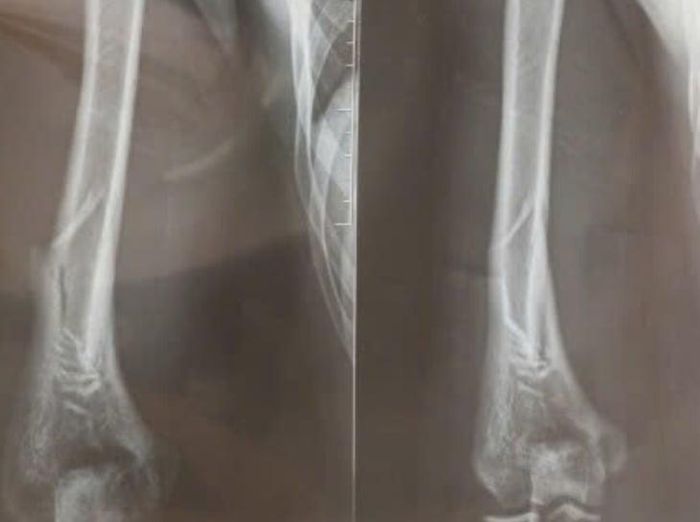

Gia đình lập tức đưa nam sinh đến cấp cứu tại Bệnh viện Đa khoa Hà Đông. Tại đây, sau khi được sơ cứu bằng cách cố định tạm thời bằng nẹp gỗ, bệnh nhân được chụp X-quang và xác định bị gãy ở vị trí 1/3 dưới xương cánh tay phải. Bệnh nhân được chỉ định phẫu thuật kết hợp xương bằng nẹp vít khóa.

Hình ảnh chụp X-quang nam thanh niên 18 tuổi gãy tay khi chơi vật tay - Ảnh: BVCC

Bác sĩ Nguyễn Trọng Nghĩa, khoa chấn thương chỉnh hình, Bệnh viện Đa khoa Hà Đông, cho biết khi vật tay, lực xoắn tập trung vào đoạn giữa thân xương cánh tay, nơi có rãnh xoắn, làm tăng nguy cơ gãy xương kiểu xoắn. Đây cũng chính là khu vực mà thần kinh quay đi qua nên nếu tổn thương lan rộng, có thể gây yếu hoặc liệt vận động các cơ duỗi của cổ tay và ngón tay.